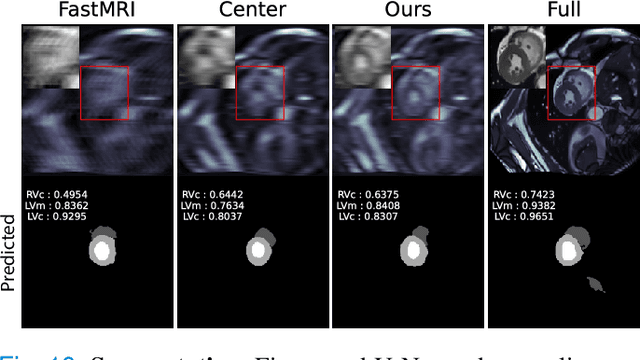

Abstract:To accelerate MRI, the field of compressed sensing is traditionally concerned with optimizing the image quality after a partial undersampling of the measurable $\textit{k}$-space. In our work, we propose to change the focus from the quality of the reconstructed image to the quality of the downstream image analysis outcome. Specifically, we propose to optimize the patterns according to how well a sought-after pathology could be detected or localized in the reconstructed images. We find the optimal undersampling patterns in $\textit{k}$-space that maximize target value functions of interest in commonplace medical vision problems (reconstruction, segmentation, and classification) and propose a new iterative gradient sampling routine universally suitable for these tasks. We validate the proposed MRI acceleration paradigm on three classical medical datasets, demonstrating a noticeable improvement of the target metrics at the high acceleration factors (for the segmentation problem at $\times$16 acceleration, we report up to 12% improvement in Dice score over the other undersampling patterns).